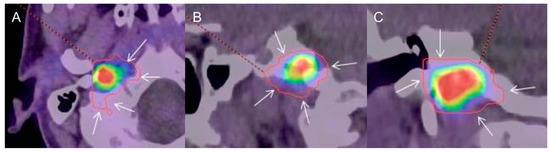

2.2. Tumor Volume Assessment

2.3. Positional GTV Assessment

2.4. Radiation Treatment Planning